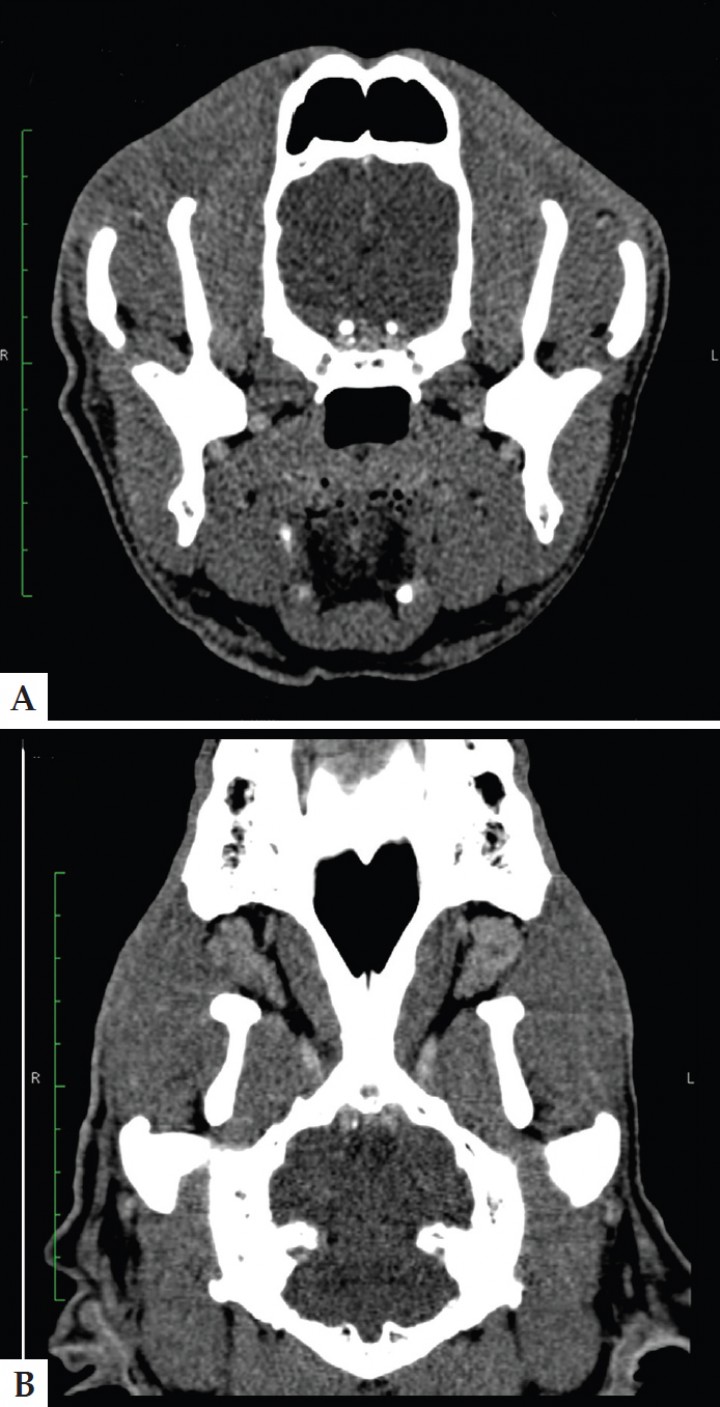

Se realizó una TC de revisión a las 4 semanas de la cirugía, en la que se confirmó la recuperación completa de la inflamación de la glándula cigomática y el absceso (Fig. 2).

<p>Imagen de tomografía computarizada con ventana de tejido blando en la revisión realizada un mes después de iniciar el tratamiento (A. Axial; B. Dorsal) en la que se puede observar la recuperación completa del absceso y sialoadenitis. Ancho de ventana 236 UH. Centro de ventana 100 UH.</p>

Imagen de tomografía computarizada con ventana de tejido blando en la revisión realizada un mes después de iniciar el tratamiento (A. Axial; B. Dorsal) en la que se puede observar la recuperación completa del absceso y sialoadenitis. Ancho de ventana 236 UH. Centro de ventana 100 UH.